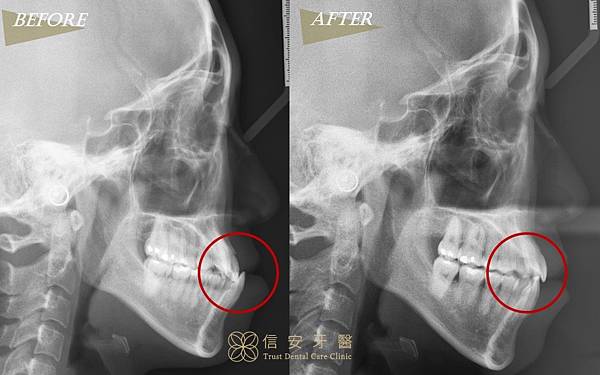

▲從X光可以看到,原本「地包天」的下顎過長問題已得到解決,變成正確的咬合囉!